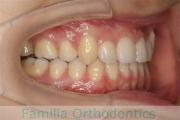

No.22V-299

- 上顎前突

- 叢生

- 30歳

- 女性

- 上:

- 44

- 下:

- 主な使用装置:

- FEA 022

- 治療にかかった費用:

- 90万円

上の出っ歯、口が閉じにくい、下の前歯のガタガタを治したいということで来院されました。上顎から左右小臼歯を、下の前歯は凹凸が非常に強いので、こちらから一本抜歯を行いました。2年強、30回程度の通院が必要でした。

成人になってからの叢生(でこぼこ、凹凸、ガタガタ)は、保定をしっかりしないと後戻りをしてしまうリスクが高いです。